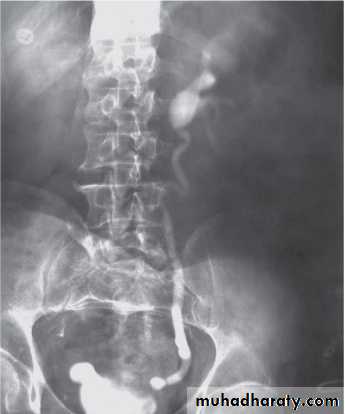

The VCUG:

the definitive examination

to diagnose and grade reflux and establish reversible causes

must include a voiding phase:

in some cases, reflux may be seen only during the elevated intravesical pressures associated with micturition.

in visualizing the urethra, may allow the diagnosis of outflow obstruction to be made (e.g., posterior urethral valves).

The intravenous urography (IVU) findings are usually normal in lower grades of reflux.

MCUG